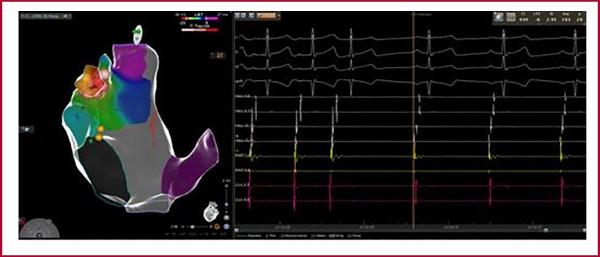

A los 9 meses la paciente continuaba sintomática, refractaria a múltiples esquemas de tratamiento médico. En el ECG Holter control, episodios de taquicardia a 177 lpm. Se solicitó angiotomografía cardíaca que evidenció OD de base ancha con su extremo superior en continuidad con la AD. Se procedió con nueva ablación. Con sistema de navegación tridimensional CARTO 3 System y catéter Pentaray® se realizó reconstrucción y mapa de activación de AD, vena cava superior y OD. Se continuó con angiografía de la OD (Figura 1A), la cual se observaba lobulada, de base ancha y con presencia de un aneurisma, de base angosta y cuerpo de alrededor de 3 cm de diámetro, móvil con los latidos. Con utilización de ecocardiografía intracardíaca (Figura 1B) se confirmó dicha anatomía y se guió la ablación. Se realizó mapa de precocidad desde la base del aneurisma hacia el interior, y se evidenció mejor precocidad dentro del mismo (-45 ms). Con catéter irrigado externo Smarttouch SF® se realizaron 5 aplicaciones en el interior del aneurisma, sin lograr cortar la taquicardia. Se procedió luego a completar aplicaciones con catéter Freezor™ Xtra (-80°C) durante 240 segundos en dicha zona, sin evidencia de corte de la taquicardia. Finalmente, se decidió realizar aislamiento eléctrico del aneurisma con catéter de RF, y se evidenció el corte de la TA a los 8 segundos de esta última aplicación (Figura 2). Luego de 30 minutos de observación, se realizó protocolo de estimulación auricular y desde el interior del aneurisma, sin inducción de taquicardia.